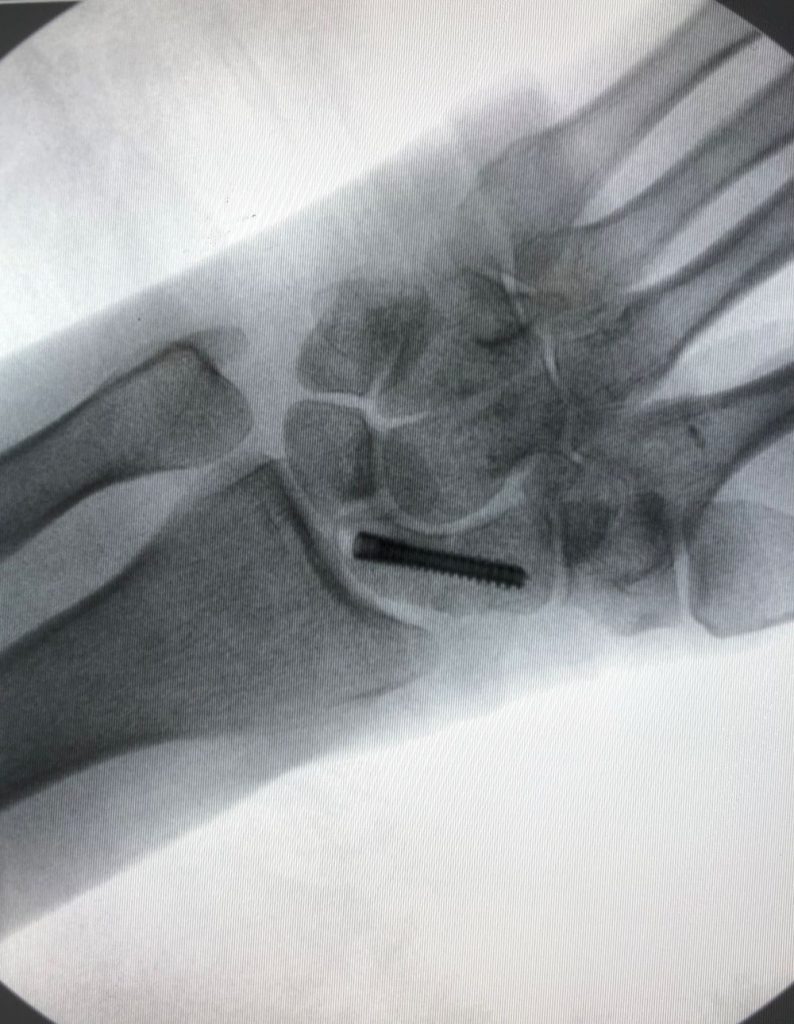

El tratamiento puede ser conservador o quirúrgico.  Dentro del tratamiento quirúrgico existen diferentes técnicas (cirugía percutánea (Figura 3), cirugía asistida por artroscopia, cirugía abierta, …), (Figura 4). Así mismo, el material utilizado puede variar también (tornillos, agujas,…).  Su Cirujano de Mano, el Dr. Polo, le recomendará la mejor opción en su caso concreto.

Figura 4 - Radiografía post-quirúrgica. Osteosíntesis percutánea con tornillo.